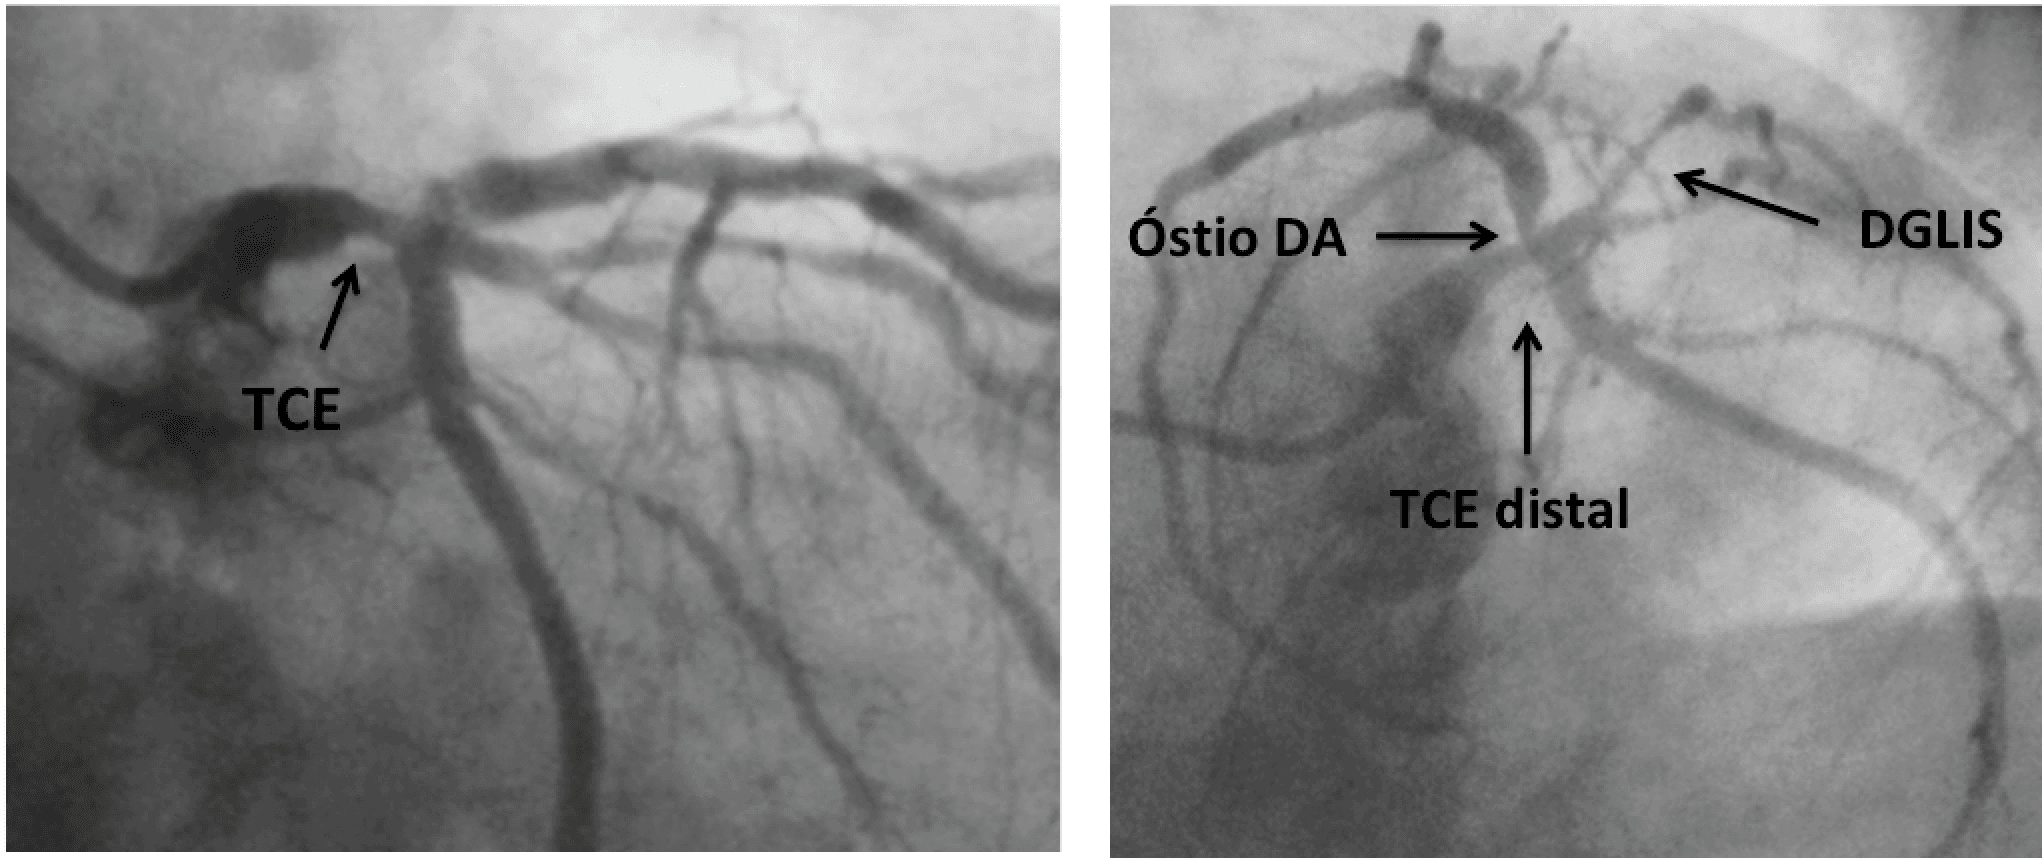

Nos anos 70 e 80, estudos randomizados que incluíram aproximadamente 200 pacientes com lesão de tronco da coronária esquerda (TCE) mostraram que a revascularização cirúrgica era superior ao tratamento…